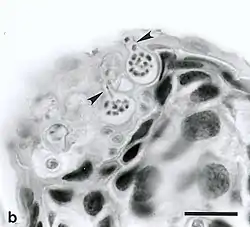

L’infection est transmise dans l’eau, par des zoospores qui colonisent la peau des amphibiens où ils forment des zoosporanges, lesquels produiront de nouveaux zoospores qui infecteront d'autres amphibiens ou d'autres parties du corps de l'animal infecté.